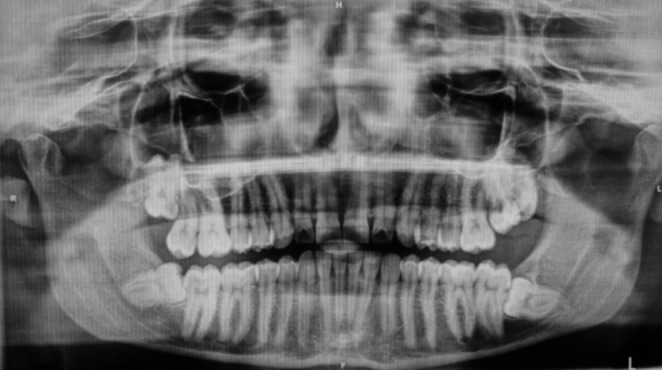

Materials and methods: The study was designed as a double-blinded, parallel group, randomized controlled clinical trial. 56 patients were divided into 2 groups: in the control group the socket was left to heal spontaneously, while the test group was treated with submucosal infiltration of i-PRF. Swelling was measured with a flexible ruler using the diagonals joining Trago and Pogonion, Gonion and labial cleft. The swelling was calculated as the sum of these diagonals before surgery, on day 3 and 7. Pain was assessed by VAS scale until the 7th postoperative day. Surgical wound healing was evaluated by the Healing Index by Landry on 3, 7 ,14 and 21st day postosperatively. The relation between duration of intervention and total swelling was also evaluated.